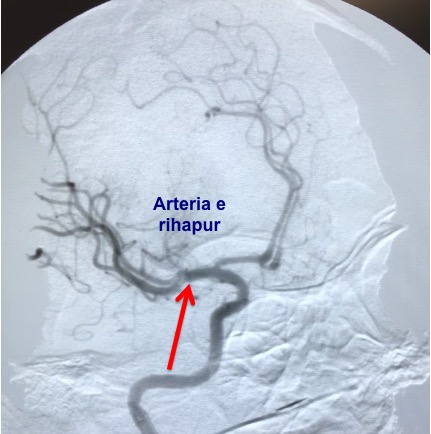

Ekipi i radiologëve për herë të parë ka përdorur stentin (retriever) për heqjen e gjakut të ngjizur (trombit )në arteriet e trurit (kokës) dhe rihapjes së qarkullimit të gjakut në tru.

Stent retriever është një produkt shumë i avansuar i cili ndihmon në kapjen dhe tërheqjen e trombit (gjakut të ngjizur) dhe rihapjes së enës së gjakut. Me rivendosjen e qarkullimit të gjakut në enën e mbyllur, mundësohet të furnizohet me ushqim dhe oksigjen pjesa e trurit e cila është e rrezikuar të dëmtohet, me çka i rikthehen funksionet të cilat filluan të humben (varësisht nga regjioni i dëmtuar i trurit).